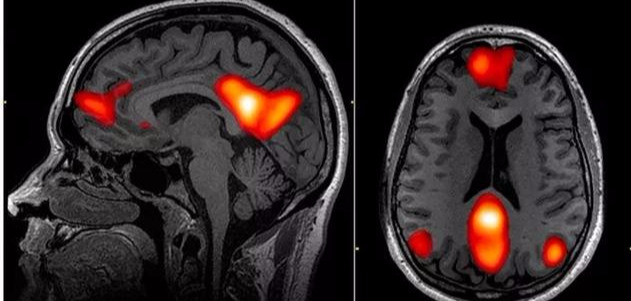

当下研究发现,其实我们大脑在思考问题时候,不是单一区域发生反应而是牵连的其他整个大脑网络产生反应。

研究发现,负责情绪调节、反刍性思维、兴趣缺失有关的奖赏回路,以及自我意识相关的大脑网络,在抑郁症病人的大脑当中都有或多或少的异常,对应到具体的位置,就是抑郁症患者大脑的杏仁核活跃程度和连接程度会增强,膝下前扣带回活跃程度会增强,而脑岛和背侧前额叶的活跃程度会降低。

不过这只是大数据下很多案例的综合,具体到每个人身上也有很多差异。